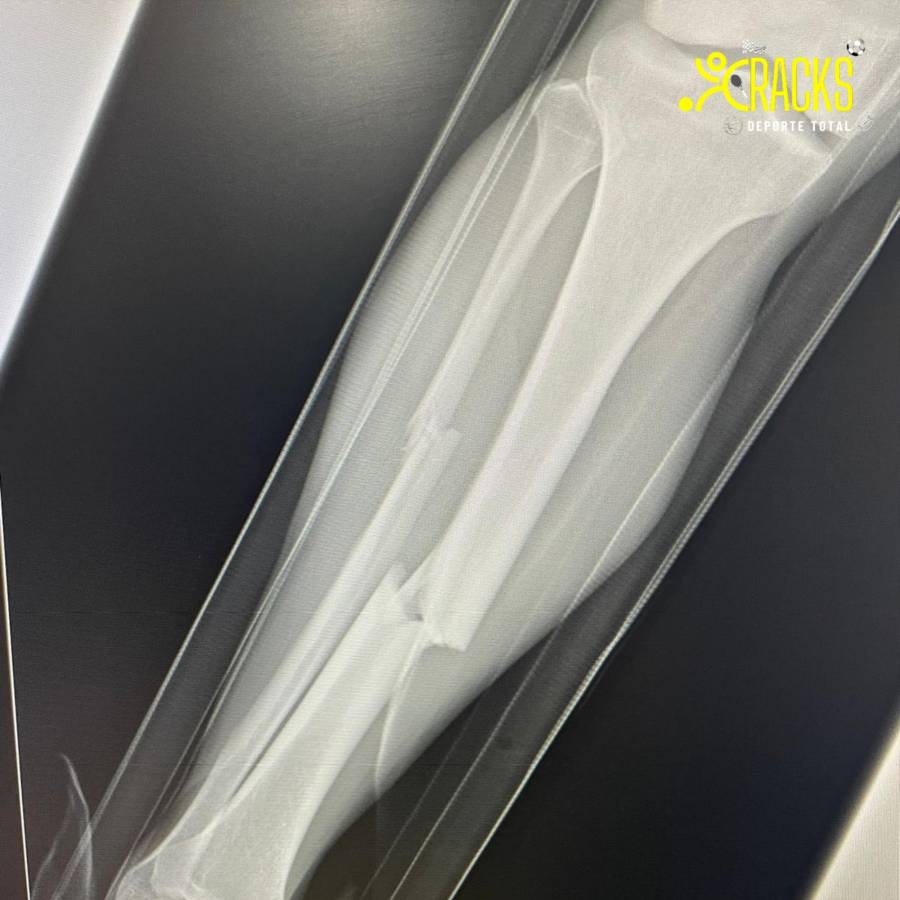

Fuentes al interior de Atlante indicaron que Christian Bermúdez sufrió fractura de tibia y peroné.

“Tras la revisión realizada por el cuerpo médico del equipo al Hobbit, el diagnóstico fue de fractura de tibia y peroné de la pierna derecha.

Christian será sometido a procedimiento quirúrgico”. publicó el club de Liga de Expansión.